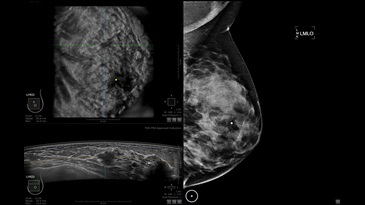

• Получение объемных 3D изображений с возможностью покадрового просмотра

• Получение изображений в поперечной плоскости (в реальном времени) и в коронарной плоскости (статическая, для указания нахождения соска)

• Отображение объемных 3D ультразвуковых изображений, которые состоят из традиционных поперечных и воссозданных коронарных и сагиттальных проекций

• Стандартизованная ориентация изображения: «толстый срез» в коронарной плоскости; поперечная; сагиттальная плоскость; радиальный и антирадиальный поворот изображения; просмотр исключительно области интереса

• Изменяемая толщина среза: 0,5 - 10,0 мм (шаг 0,5 мм)

• Срез: 0,5 - 2,0 мм (шаг 0,5 мм)